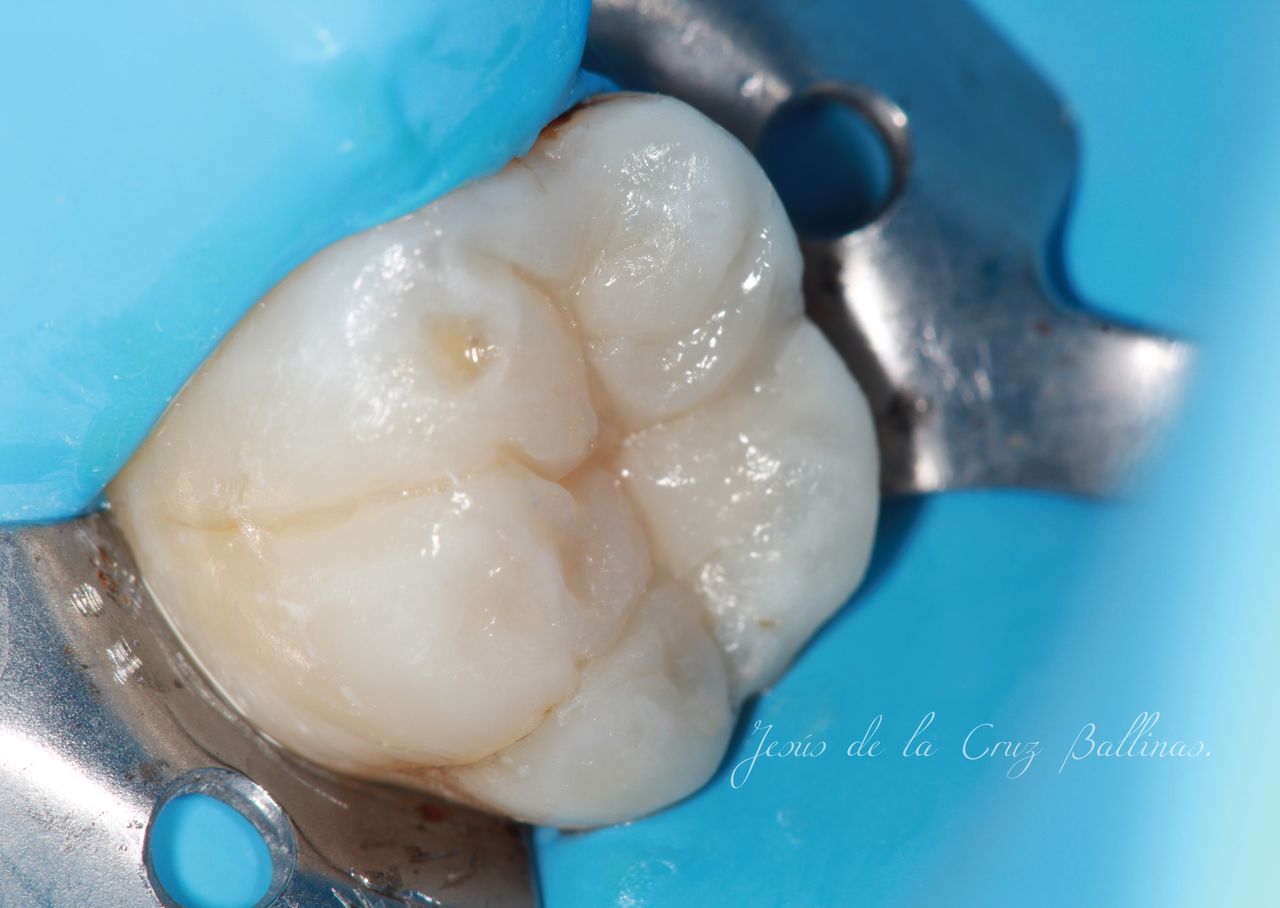

La especialidad en Endodoncia esta enfocada en prevenir, diagnosticar y tratar las enfermedades pulpares y perirradiculares de los dientes. Entre los problemas más comunes tratamos dolores dentales, infecciones dentales agudas y crónicas para evitar la extracción dental y preservar la función del órgano dentario.

• Endodoncia

• Rehabilitación bucal